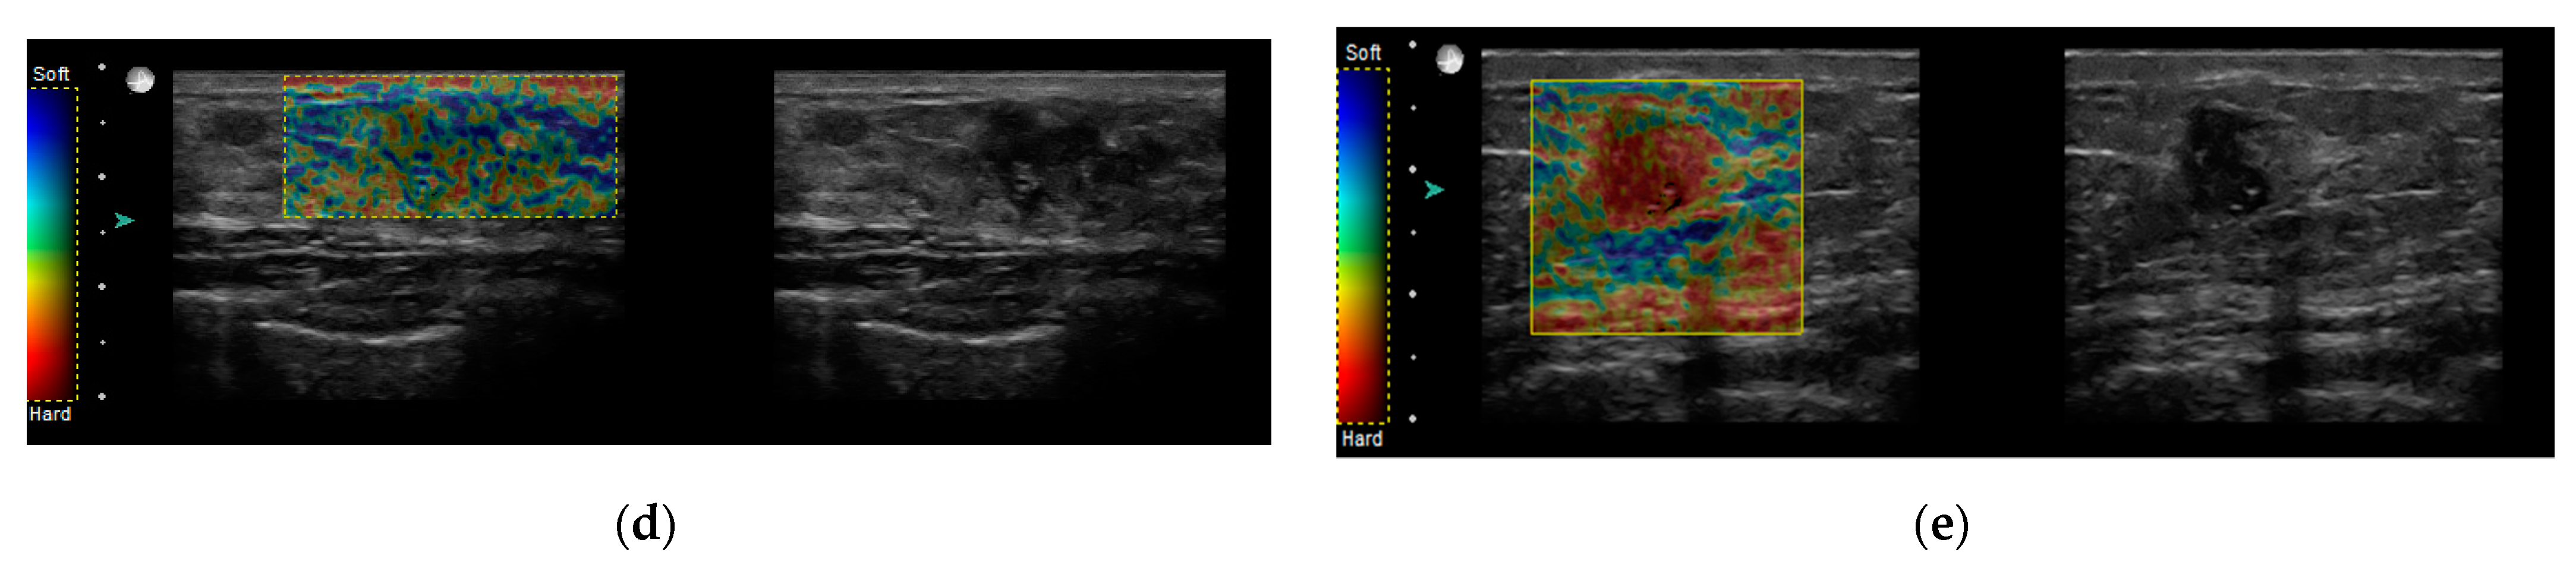

2.2. Sonoelastography